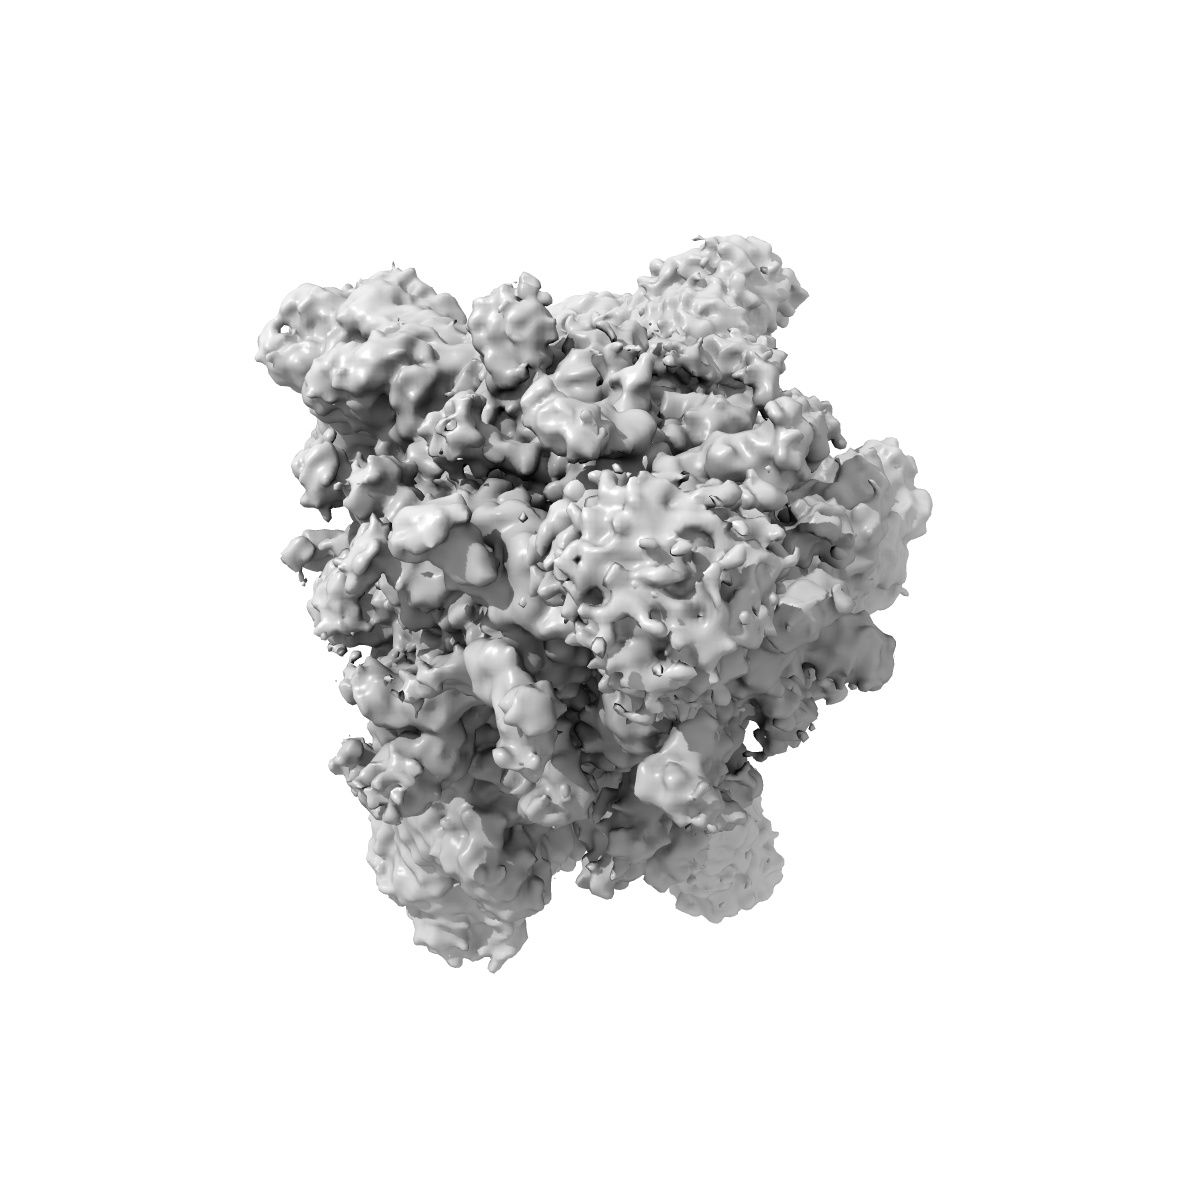

State 2 of SARS-CoV-2 XBB Variant Spike protein trimer complexed with antibody PW5-5

Single-particle3.21 Å

Sample: SARS spike protein (S) in complex with broadly neutralizing antibody PW5-5

Potent and broadly neutralizing antibodies against sarbecoviruses induced by sequential COVID-19 vaccination.